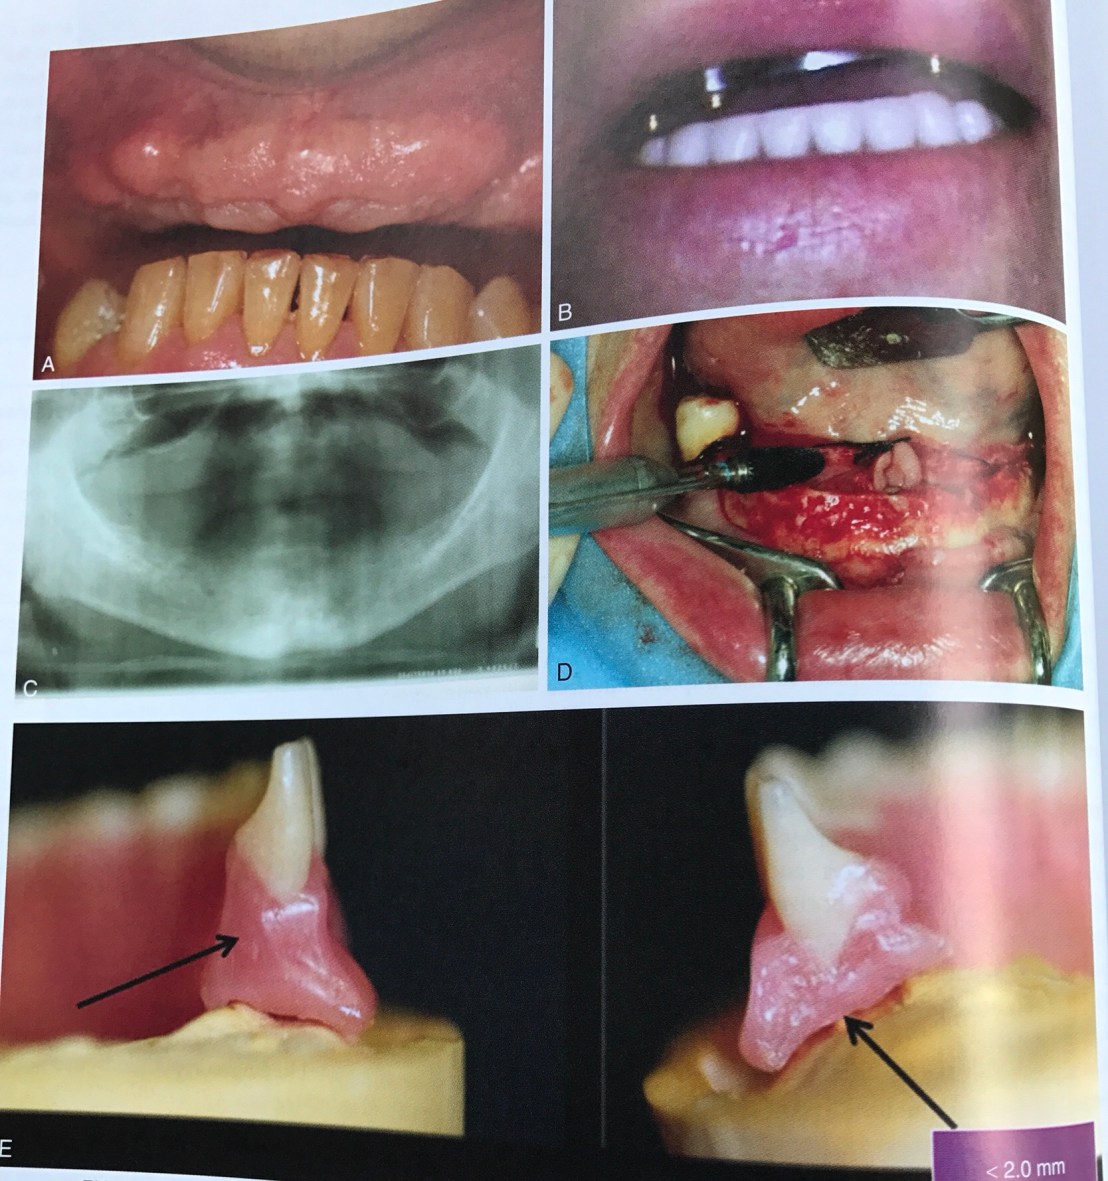

แสดงการสึกของ Canine ล่าง และ notch ที่ฟันคู่สบ 22 –> มี Bruxism

รูปล่าง เวลาทำ Working contact พบ Canine บนสบกับ 34 และสังเกตว่า คอฟันซี่ 34 เกิด abfraction–> แสดงถึง Parafunction

ดังนั้นเวลาที่เราต้องทำ Pros ในฟันหลัง จะต้องปรับแต่งการสบฟัน ไม่ให้เกิดลักษณะนี้ด้วย

ในคนไข้ที่มีฟันหน้าล่างสึก (Bruxism) แบบนี้ เราต้อง restore ฟันหน้าล่างขึ้นมาก่อน เพื่อให้เกิด Anterior guidance ที่ปกติ จึงจะสร้าง Prosthesis ในฟันหลังได้ (หมายความว่า ถ้าเราสร้าง Pros ขึ้นมาโดยไม่สนตำแหน่งฟันหน้า Pros จะ failure ไปด้วย)

แสดงตำแหน่ง Ideal คือ ปลาย Implant ห่างจาก nerve มากกว่า 2 มม.

Software แสดง Safety zone

ทำไมต้องเป็น 2 มม.?

คำตอบคือ injury ชนิด Neurapraxia สามารถเกิดขึ้นได้จาก Compression necrosis ระยะที่ใกล้ไม่ถึง 2 มม. แม้ไม่ invade nerve โดยตรง แต่แรงจากการกดจะส่งผ่านกลไก Compression-related injury ได้